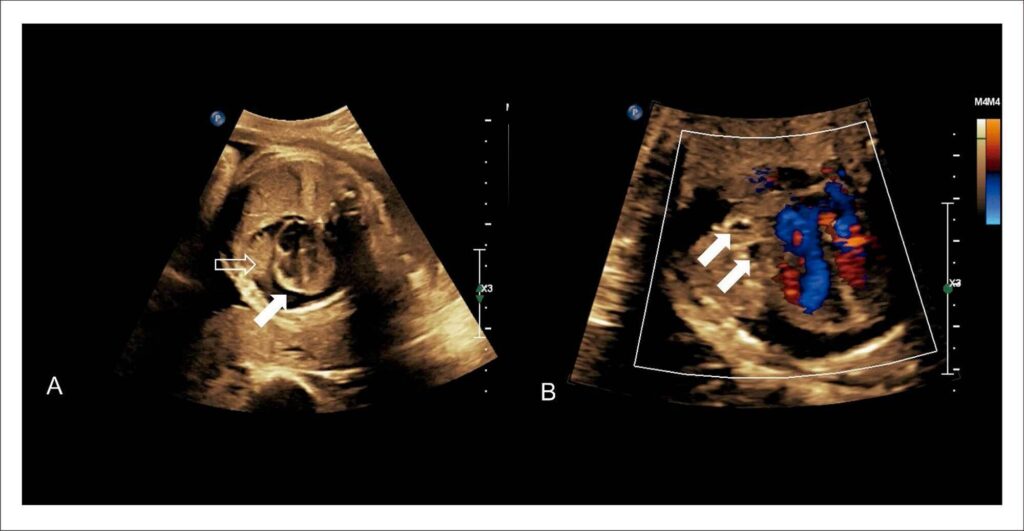

Fetal Intrapericardial Teratoma: Diagnostic and Therapeutic Challenges

Teratomas, although they are usually benign, can have embryonic origin in one or more of the 3 germ layers, resulting in complex histology, with the possibility of simultaneous areas of mature and immature tissue. Intrapericardial teratomas are tumors with a low incidence, but they frequently invade the mediastinum and compress adjacent structures, leading to death. We report a case of intrapericardial teratoma diagnosed in a fetus at 22 weeks of gestation.